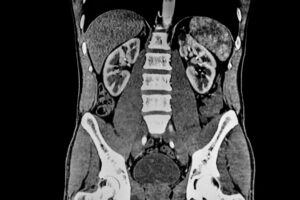

MRT Darstellung der Leber und Gallenwege

Die MRT ist aufgrund des guten Weichteilkontrastes, leberspezifischem Kontrastmittel (mehr dazu unten). Sie kommt sowohl in der Erstdiagnostik als auch in der Verlaufskontrolle zum Einsatz. Sie kommt unter anderem zum Einsatz bei:

- Leberläsionen und Raumforderungen: durch den hohen Weichteilkontrast und die diffusionsgewichtete Bildgebung ist die MRT das Verfahren der Wahl um eine Differenzierung von Leberläsionen zu ermöglichen. Bei einem hepatozellulären Karzinom ist bereits durch eine MRT-Untersuchung mit Kontrastmittel eine Abschätzung des Ausbreitungsgrades möglich. Ebenfalls ist eine Beurteilung des Therapieansprechens und dadurch auch eine prognostische Einschätzung möglich